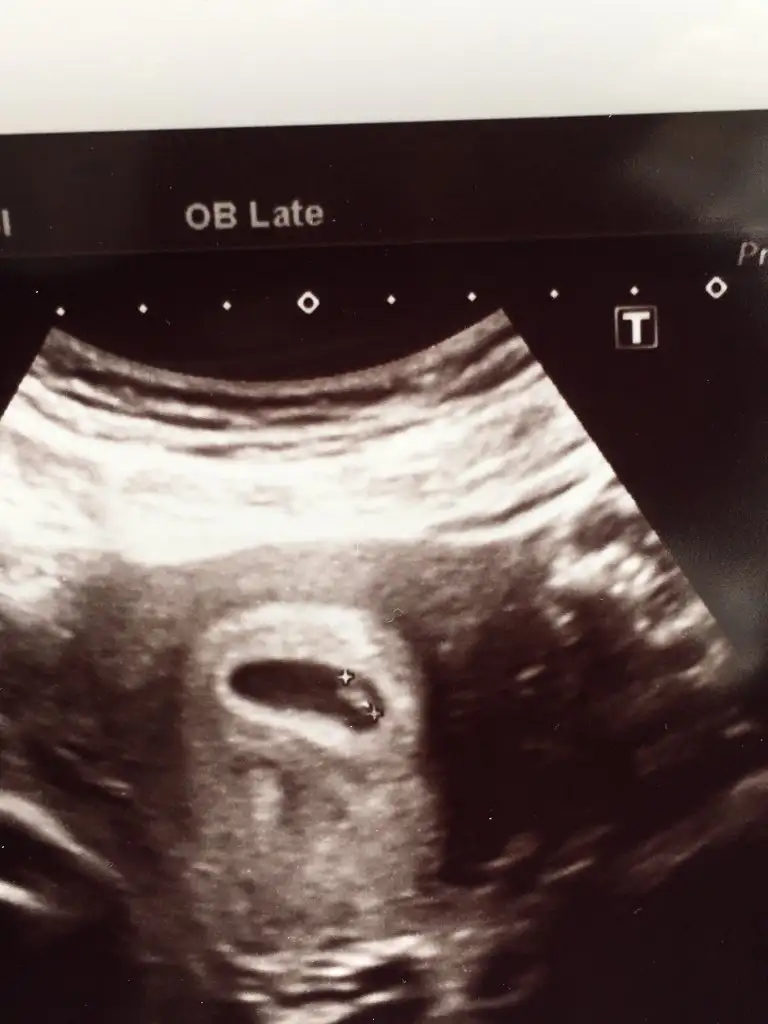

Ay ciddimisin bi yaşıma daha girdim şuna bi bakabilirmisiniz ilk çocuğumun resimleri cinsiyetini bilirse 2. Çocuğumun cinsiyetini daha erken öğrenebileceğim, çok heyecanlandım şimdidenKızlar bı arkadaş keseye göre tahmin yapıyor ve hep tutuyormuş iki oğlunu da bu şekilde cok yeniyken bile tahmin etmiş...ogullarinda kesesi hep uzunmuş muz gibi...yuvarlak ve yuvarlağa yakın olanlar hep kızdır diyor..ve bayağı emin konusuyor..benimki şişman bı fasulye gibi oo kesin kız görürsün dedi...sizlerin keselerinin şekli nasıldı ve cinsiyet neydi konusalimmi

Kesenin ucu mu yuvarlak ya da uzun olacak. 5 haftalık benim bebeğim kesenin ucunda muz gibi bir uzantı varKızlar bı arkadaş keseye göre tahmin yapıyor ve hep tutuyormuş iki oğlunu da bu şekilde cok yeniyken bile tahmin etmiş...ogullarinda kesesi hep uzunmuş muz gibi...yuvarlak ve yuvarlağa yakın olanlar hep kızdır diyor..ve bayağı emin konusuyor..benimki şişman bı fasulye gibi oo kesin kız görürsün dedi...sizlerin keselerinin şekli nasıldı ve cinsiyet neydi konusalimmi